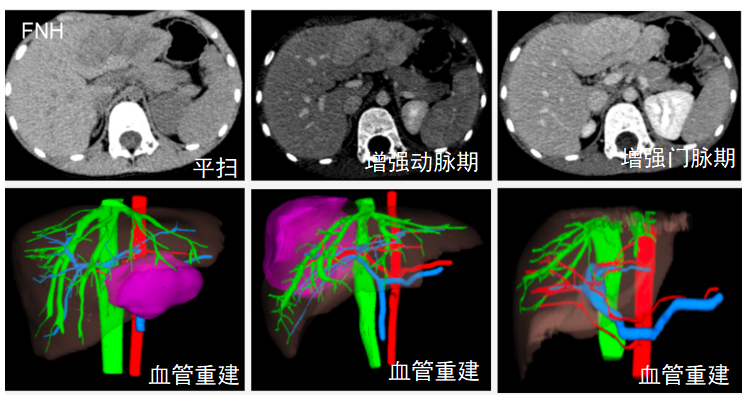

帮助诊断医生区分肿瘤类型(如肝母细胞瘤vs肝婴儿型血管瘤)。

CT增强扫描应用于病变性质鉴别

A.CT平扫+增强扫描检查后诊断为:肝母细胞瘤

B.CT平扫+增强扫描检查后诊断为:肝婴儿型血管瘤

CT增强扫描应用于临床手术方案制定(肝肿瘤术前方案制定)